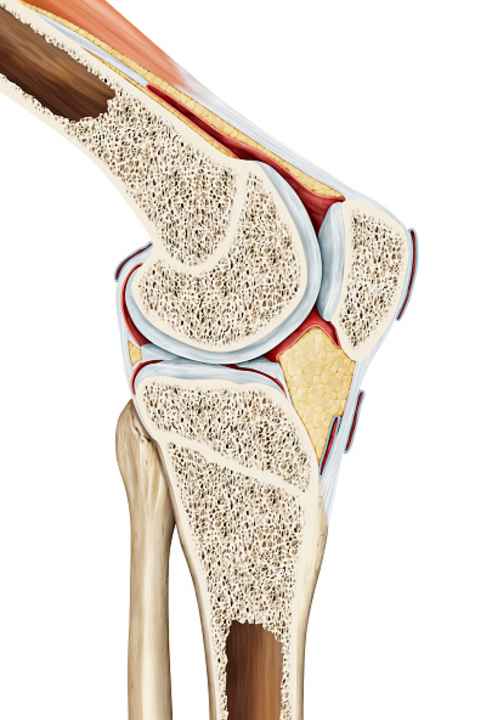

Healthy cartilage tissue does not have blood vessels running through it, but must be supplied with nutrients by the synovial fluid. So if you pedal regularly, you ensure that your knee is nourished and therefore healthy. If the joint moves evenly on a fixed circular path, the knee is less stressed by twisting movements than with other movements. However, a knee is not just made up of cartilage, but is a highly complex "component" of the body. And not all cycling is the same. It makes a huge difference to the knees whether they are moved evenly on an ergometer or rumbling through the terrain on a mountain bike.

Everyone has heard this statement before. In principle, it is true, but as is so often the case with medical advice, it is not so easy to generalise. Viewed in isolation, the circular movement of the knee is actually good for its health. Cycling sets the fluid in the knee in motion. Pedalling pumps synovial fluid through the knee, which is particularly important for the cartilage inside.